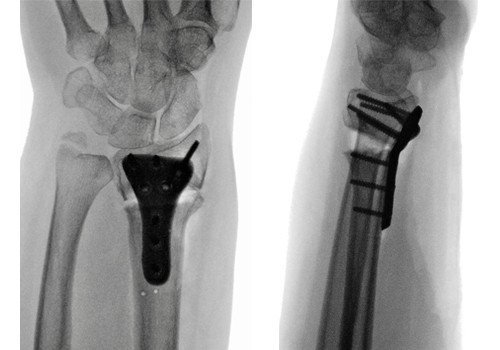

Fall 1: Korrektur eines fehlverheilten Speichenbruches am Handgelenk nach Unfall vor 8 Monaten

Nach erfolgter Korrektur des betroffenen Knochens oder Gelenkes fixieren wir diese in korrekter anatomischer Stellung mit Platten und Schrauben. Im Einzelfall werden diese Platten individuell auf die persönliche Anatomie des Patienten angepasst und sogar mit spezifischen 3D-Druckern als Titanimplantat individuell hergestellt. Unsere Abteilung hat als Mitentwickler dieses Verfahren bereits langjährige Erfahrung und somit entsprechende Expertise (erster Eingriff mit solch einem Verfahren im Jahr 2016). Welches operative Verfahren angewendet wird, wird im Einzelfall individuell besprochen und geplant.